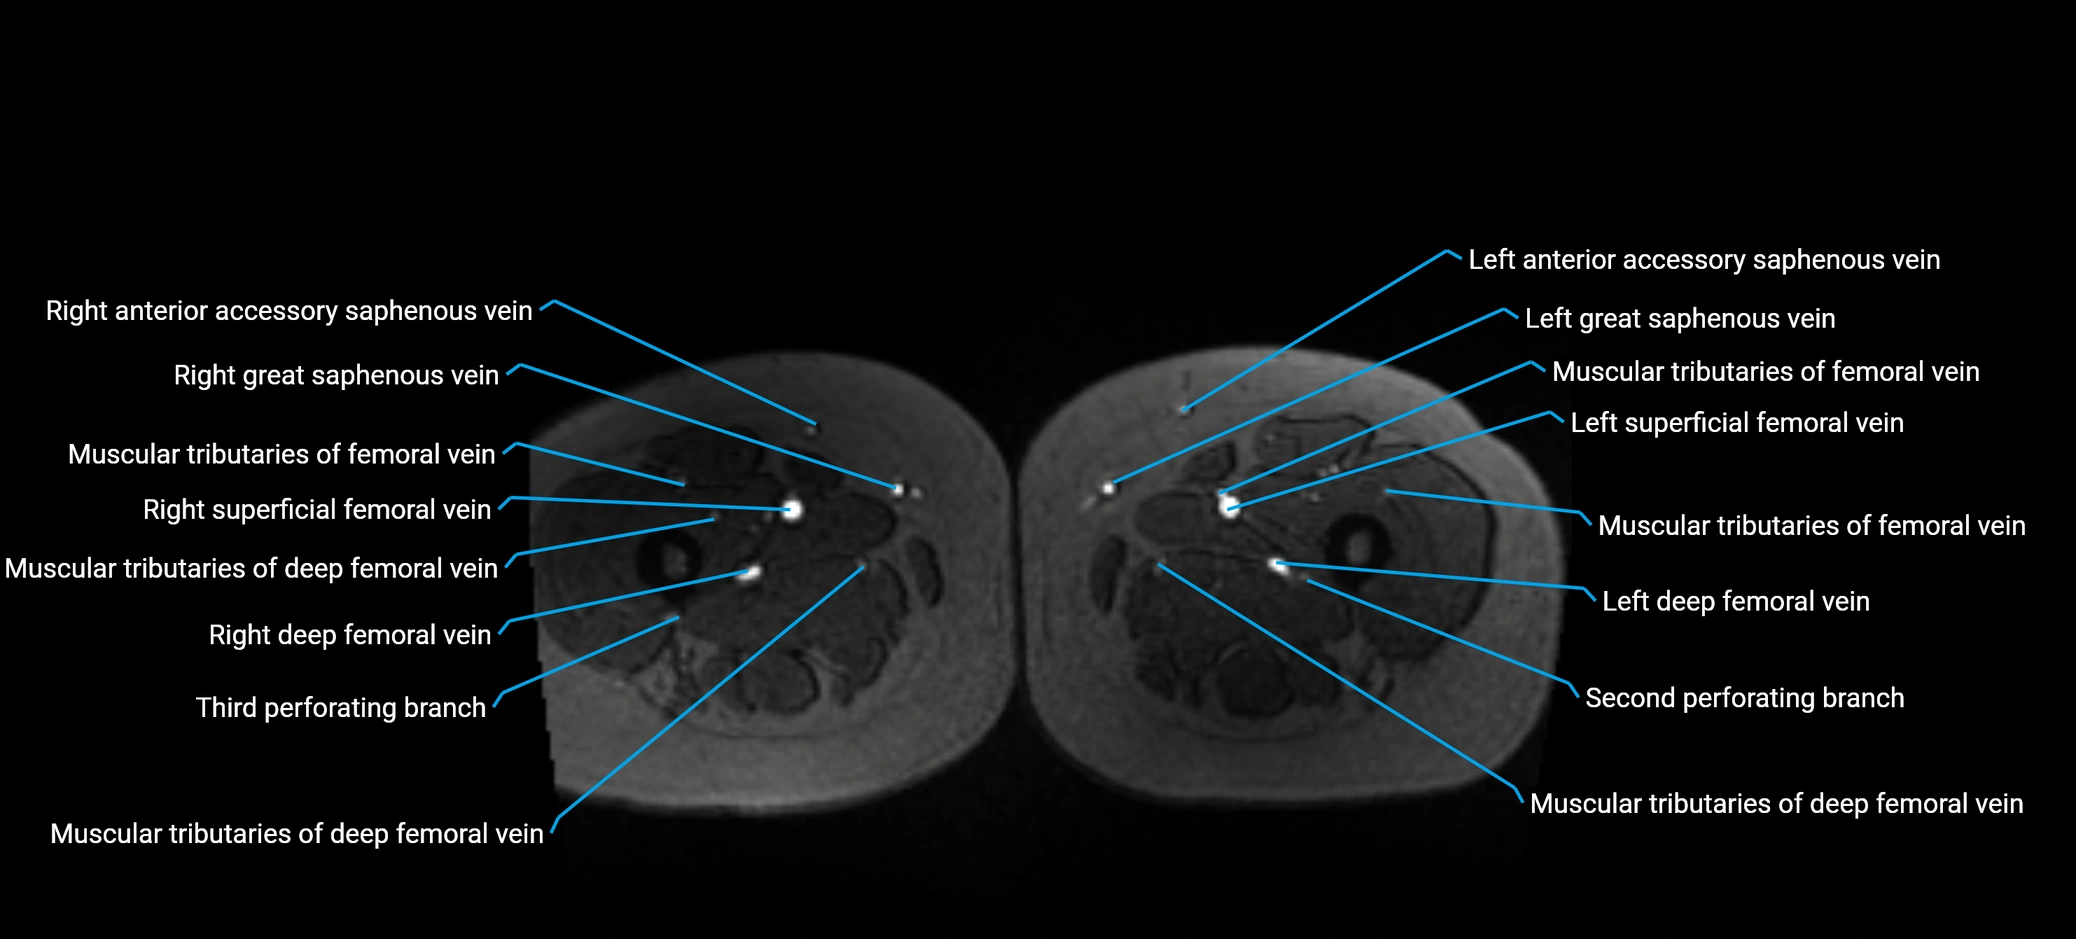

MRI image

image